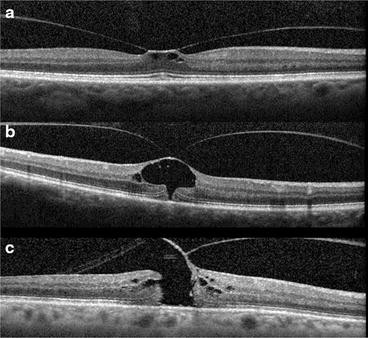

Surgical outcomes, intraoperative complications, and postoperative complications in patients undergoing vitrectomy for VMT following use of ocriplasmin have been favorable (Fig. 3). In a multicenter, controlled interventional series, Greven et al. retrospectively evaluated visual acuity and surgical outcomes in 51 eyes of 51 patients undergoing vitrectomy for VMT or FTMH who had already been treated with ocriplasmin. Outcomes were compared to a control group comprised of 22 eyes of 22 patients who had been offered ocriplasmin but chose vitrectomy alone. Anatomic success (release of VMT or closure of FTMH) was achieved in 98% (50/51 eyes) of eyes in the ocriplasmin treated group and 100% (22/22 eyes) in the control group. At 6 months, the mean change in vision was similar between the ocriplasmin and control groups (−0.17 versus −0.23 LogMAR, p = 0.57).

Surgical closure of macular hole after prior treatment with ocriplasmin. A 6- year-old phakic male with medium sized FTMH (a). Visual acuity was 20/100 at baseline. Following intravitreal injection of ocriplasmin, the macular hole enlarged and VMT did not release (b). Vision worsened to 20/400. Following vitrectomy surgery, macular hole closure was achieved and vision improved to 20/80 (c) as shown on post-operative day 60